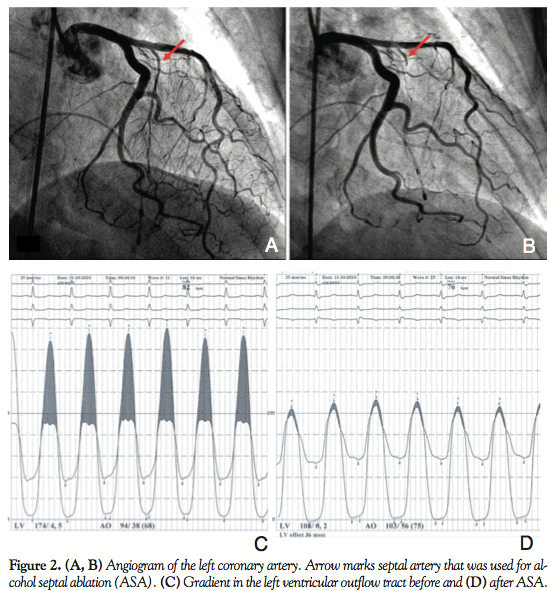

Therapy with beta-blockers was started; however, it didn’t lead to any significant subjective improvement. Therefore, angiography was indicated 6 months later with normal findings in both coronary arteries and a suitable septal artery was identified. ASA was subsequently performed using 1 mL of 96% alcohol with an immediate gradient reduction during the procedure (the invasive peak gradient decreases from 60 mm Hg to 10 mm Hg) (Figure 2). ASA led to development of right bundle branch block that remained stable and no atrioventricular conduction block developed during follow-up. Echocardiography confirmed optimal location of the ablation lesion with greater reduction in the midventricular part of the septum. Due to persistence of the SAM phenomenon, the patient was kept on beta-blockers. Decrease of the LVOT gradient after ASA led to a significant improvement of symptoms: angina disappeared completely and only mild dyspnea (NYHA class 1-2) was present during the first 6 months.

However, 1 year later, the patient presented with a new worsening of dyspnea and manifestation of angina with slow progression to NYHA class 3 and CCS class 2 again. Transthoracic echocardiography performed 14 months after ASA revealed significant subaortic obstruction with SAM. Based on CW Doppler, the subaortic gradient was 26 mm Hg at rest, but it increased up to 200 mm Hg after nitrate provocation. The ASA lesion was smaller and located slightly distally to the subaortic maximum (Figure 3). The location of the septal bulge with regard to the arterial supply didn’t allow performance of a new ASA and performance of surgical myectomy was therefore discussed with the patient. However, the patient refused surgical treatment and therefore ERASH was offered to the patient as an option. After providing detailed information about the procedure, its potential risks, and possible complications, the patient gave and signed informed consent.